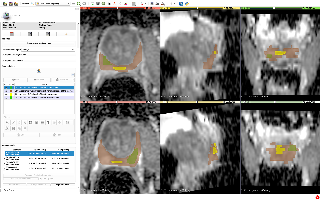

### Lung-PET-CT-Dx

| 名称 | 标注内容 | 类型 | 模态 | 数量 | 标签格式 | 文件格式 |

| - | - | - | - | - | - | - |

| [Lung-PET-CT-Dx](https://wiki.cancerimagingarchive.net/pages/viewpage.action?pageId=70224216) | 肺癌 | 目标检测 | CT | 363 | xml | dcm |